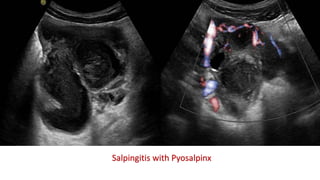

This document discusses the evaluation of right lower abdominal pain and lists appendicitis as a key cause. It notes that other potential causes include hemorrhagic cysts, heterotrophic pregnancy, salpingitis with pyosalpinx, funiculitis, and torsion of an undescended testis. The document was presented by Dr. A.S.M. Sufian of Cumilla Medical College Hospital and thanks the audience for their patience and listening.